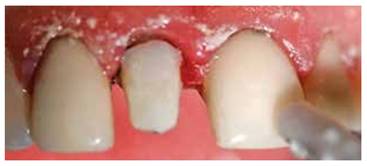

Paciente masculino de 36 años de edad sin antecedentes patológicos personales (A.P.P.) se presenta al Postgrado de Endodoncia de la Universidad Latina de Costa Rica por motivo de Trauma Dental debido un accidente laboral, el hecho ocurrió tres días anterior a su visita al centro de atención. Clínicamente se observa inflamación y un grado de movilidad II. Desalojo incisal y fuera de oclusión. (Figur 3) Radiográficamente se observa una obturación deficiente del conducto y a la vez una aparente fractura radicular. (Figura 4)

Figura 3: Inflamación de tejidos blandos y movilidad grado II de pieza 1.1, desalojamiento del alveolo y fuera de oclusión.